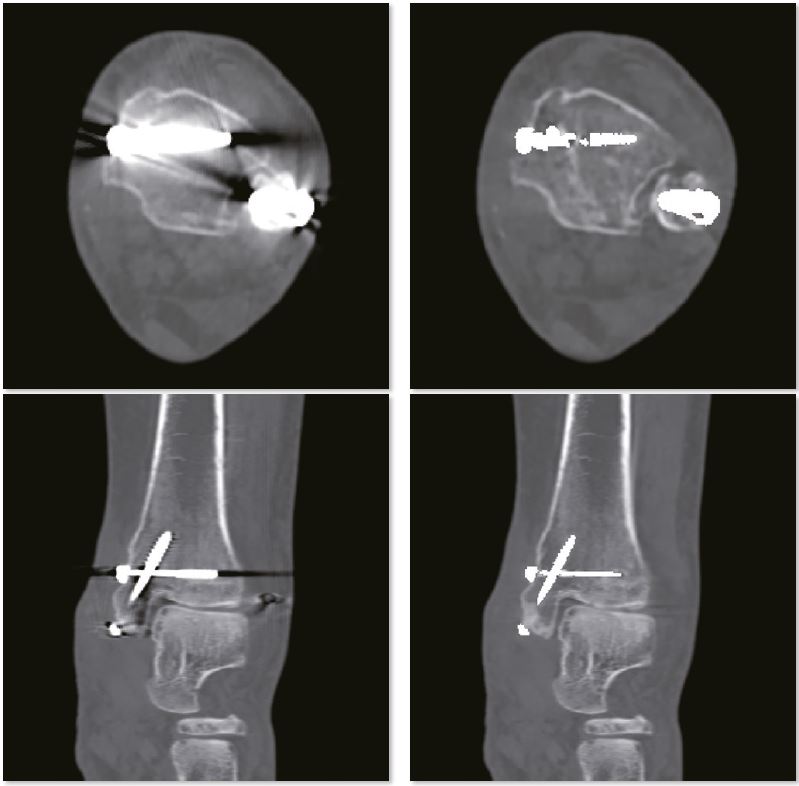

Лікоть з внутрішньою фіксацією

Металеві артефакти більше не є перешкодою для точної післяопераційної оцінки переломів за допомогою пристроїв внутрішньої фіксації. Незрощення перелому проксимального відділу променевої кістки дуже детально показано на реконструкції SEMAR.

Звичайне зображення

Зображення з SEMAR

Післяопераційний гомілковостопний суглоб

Зображення SEMAR чітко демонструють перелом малогомілкової кістки. Без SEMAR перелом прихований артефактами, які заважають діагностиці. Крім того, точні положення пристроїв внутрішньої фіксації можна чітко оцінити без артефактів на зображеннях SEMAR.

Звичайне зображення гомілковостопного суглобу

Зображення гомілкостопного суглобу з SEMAR